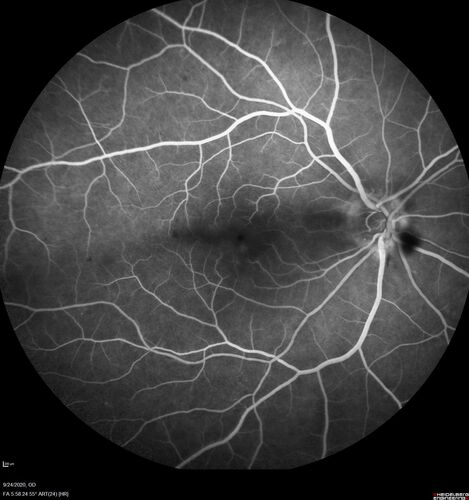

Elevated Episcleral Venous Pressure and Retinal Hemorrhages in both eyes

78 year old female with chronic red eye.   The eyes are red all the time now.  She is on Xeralto because of a history of blood clots in her lungs (2005 about).  She has not had problems since.  She has had floaters for many years.  Ever since her eyes got funny she sees more floaters in both eyes.  She had a brain scan over 6 months ago which was OK.  She also had double vision when this first started which went away.  She could not drive for a few months.

VA OD: Dcc20/32-1

VA OS: Dcc20/125

IOP: TP: OD:17 OS:16

Neuroimaging did not show a CC fistula